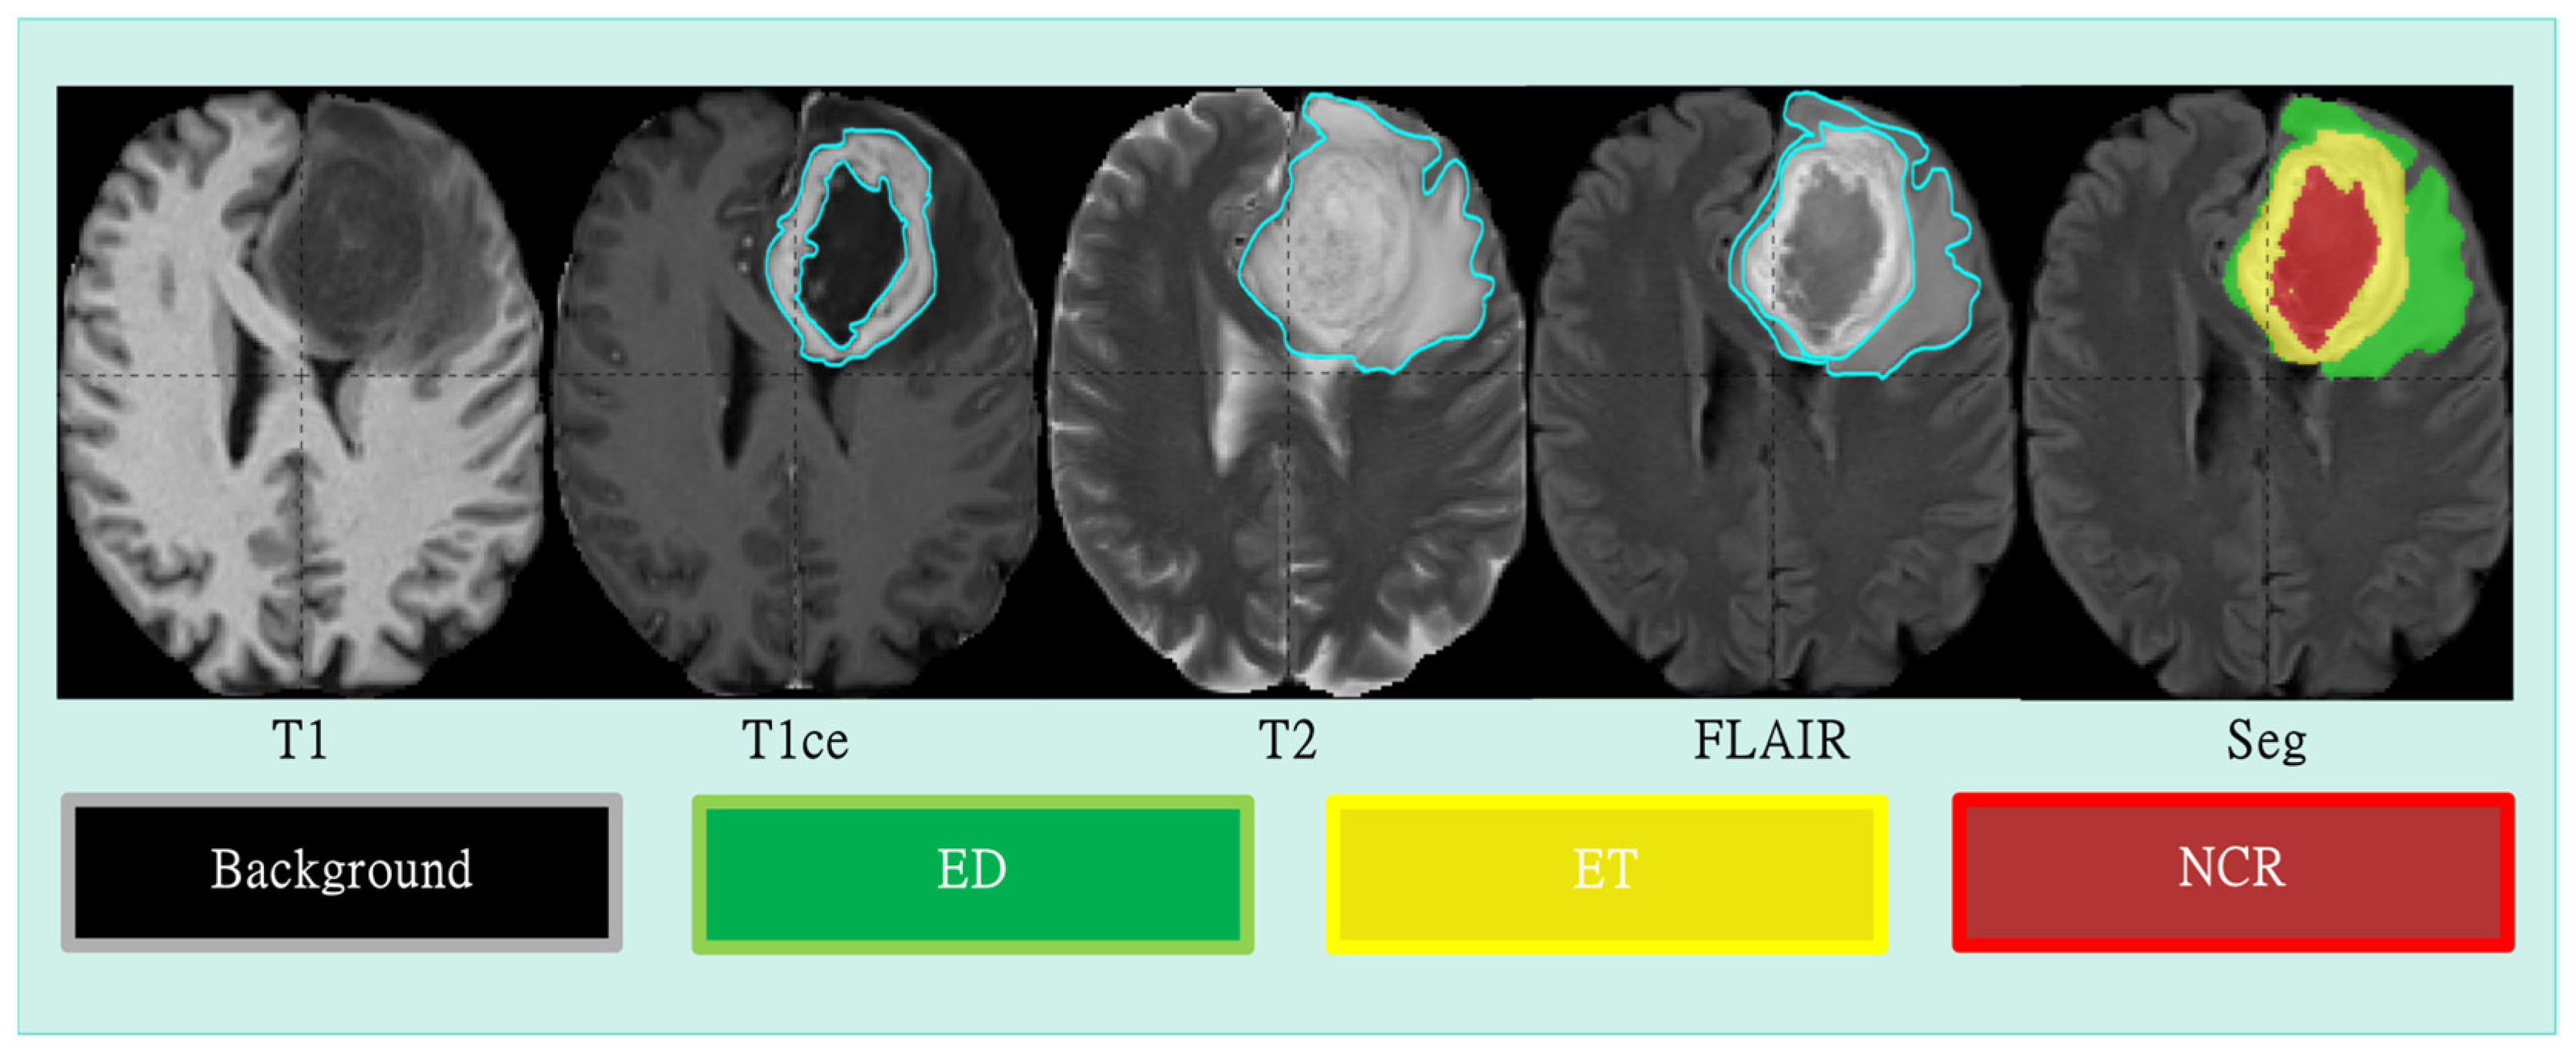

4.1. Datasets and Preprocessing